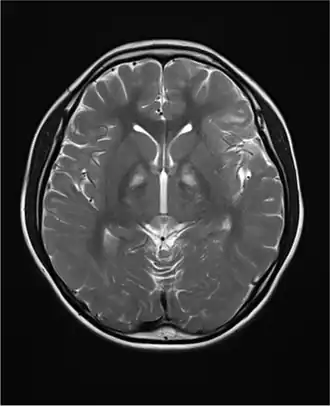

Le syndrome de Kearns-Sayre est une maladie neuromusculaire (myopathie, ophtalmoplégie), due à des délétions de l'ADN mitochondrial : de 1,3 à 8 kilobases (souvent 5 kb). Ce sont des délétions très souvent sporadiques, et donc hétéroplasmiques.

La maladie est principalement caractérisée par une ophtalmoplégie externe progressive[1] et une dégénéscence de la couche pigmentaire de la rétine, une anomalie de la conduction cardiaque et une ataxie[3]. À un moindre degré, on peut observer une démence, une surdité et un diabète.